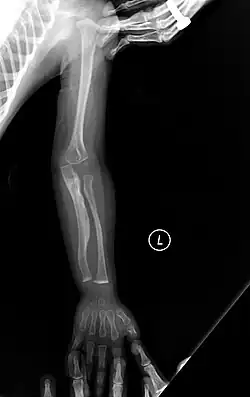

The main symptom of osteogenesis imperfecta is fragile, low mineral density bones; all types of OI have some bone involvement.[5] In moderate and especially severe OI, the long bones may be bowed, sometimes extremely so.[28] The weakness of the bones causes them to fracture easily—a study at the Endocrine Unit at the National Institute of Child Health in Karachi, Pakistan found an average of 5.8 fractures per year in untreated children.[29] Fractures typically occur much less after puberty, but begin to increase again in women after menopause and in men between the ages of 60 and 80.[1]: 486

- Type V – Having the same clinical features as type IV, it can be clinically distinguished by observing a "mesh-like" appearance to a bone biopsy under a microscope. Type V can be further distinguished from other types of OI by the "V triad": an opaque band (visible on X-ray) adjacent to the growth plates; hypertrophic calluses (abnormally large masses of bony repair tissue) which form at fracture sites during the healing process; and calcification of the interosseous membrane of the forearm,[50] which may make it difficult to turn the wrist.[1]: 429 Other features of this condition may include pulled elbow, and, as in other types of OI, long bone bowing and hearing loss.[64] Cases of this type are caused by mutations in the IFITM5 gene on chromosome 11p15.5.[64][49] The separation of type V from type IV OI, its clinical type, was initially suggested even before its genetic cause was known, by Glorieux et al. in 2000.[50][65] Type V is relatively common compared to other genetically defined types of OI—4% of OI patients at the genetics department of the Brazilian Hospital de Clínicas de Porto Alegre were found to have it.[66]

Diagnosis is typically based on medical imaging, including plain X-rays, and symptoms. In severe OI, signs on medical imaging include abnormalities in all extremities and the spine.[97] As X-rays are often insensitive to the comparatively smaller bone density loss associated with type I OI, DEXA scans may be needed.[5]: 1514

An OI diagnosis can be confirmed through DNA or collagen protein analysis, but in many cases, the occurrence of bone fractures with little trauma and the presence of other clinical features such as blue sclerae are sufficient for a diagnosis. A skin biopsy can be performed to determine the structure and quantity of type I collagen. While DNA testing can confirm the diagnosis, it cannot absolutely exclude it because not all mutations causing OI are yet known and/or tested for.[83]: 491–492 OI type II is often diagnosed by ultrasound during pregnancy, where already multiple fractures and other characteristic features may be visible. Relative to control, OI cortical bone shows increased porosity, canal diameter, and connectivity in micro-computed tomography.[98] OI can also be detected before birth by using an in vitro genetic testing technique such as amniocentresis.[99]